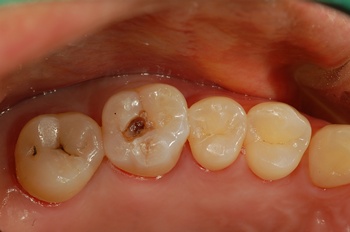

충치의 진행단계를 간단하게 설명하면, 1단계는 충치가 법랑질에 국한되어 자각증상이 거의 없다. 2단계는 충치가 상아질까지 진행된 경우로 통증은 없지만, 차가운 냉수를 마실 때 자극에 의해 이가 시린 증상이 나타난다. 3단계는 충치가 치수까지 진행된 상태로, 치수에 염증이 생기고 심한 통증이 따르게 된다. 마지막으로 4단계는 3단계에서 더 진행되어 치관이 붕괴되고 치근만 남아 있는 경우로, 이 경우 더 이상의 치아 보존이 어려우므로 이 경우 충치치료를 위해 치아를 발치해 임플란트에 이르게 된다.

충치를 판단하는 기준은 치과의사가 구강용 탐침으로 검사하여 거칠거나 소프트한 느낌, 끈적한 느낌이 나는 경우 충치로 판단한다. 이 외, 충치용 염색약으로 진단하기도 하는데 과잉반응으로 건전한 치아까지 충치로 나타나는 경향이 있어 잘 사용하지 않는다. 씹는면에 검은 점이나 검은 선이 보이는 경우, 대부분은 충치가 맞지만 단순한 치아변색일 수 도 있다고, 연세대임상지도교수출신의 박노제 원장(선릉역 이오플러스치과 대표원장)은 설명한다.

치아 우식 정도에 따라 치료방법은 다양하다. 충치가 있는 부분만 긁어내는 방법의 인레이(금, 레진, 아말감), 충치가 너무 깊어 신경치료를 하거나 충치가 너무 넓은 경우 보철물로 크라운(금, 세라믹)을 하게 된다. 그렇다면 충치치료 어떻게 해야 올바른 치료일까?

박원장은 “충치의 진행단계중 초기 충치인 경우는 충치 치료없이도 올바르게 양치하고 정기적으로 관리하면 더 이상 진행이 안될 수 있다. 재광화라는 작용으로 입 속의 칼슘과 인성분이 에나멜에 침착하여 치아구조를 회복시켜주는 다시 단단한 치아표면으로 된다. 이 경우 충치치료를 위해 치아를 삭제하는 것 보다는 정기적인 검진과 청결한 구강위생관리가 더 좋은 해결책이 될 수 있다”고 덧붙여 강조했다.